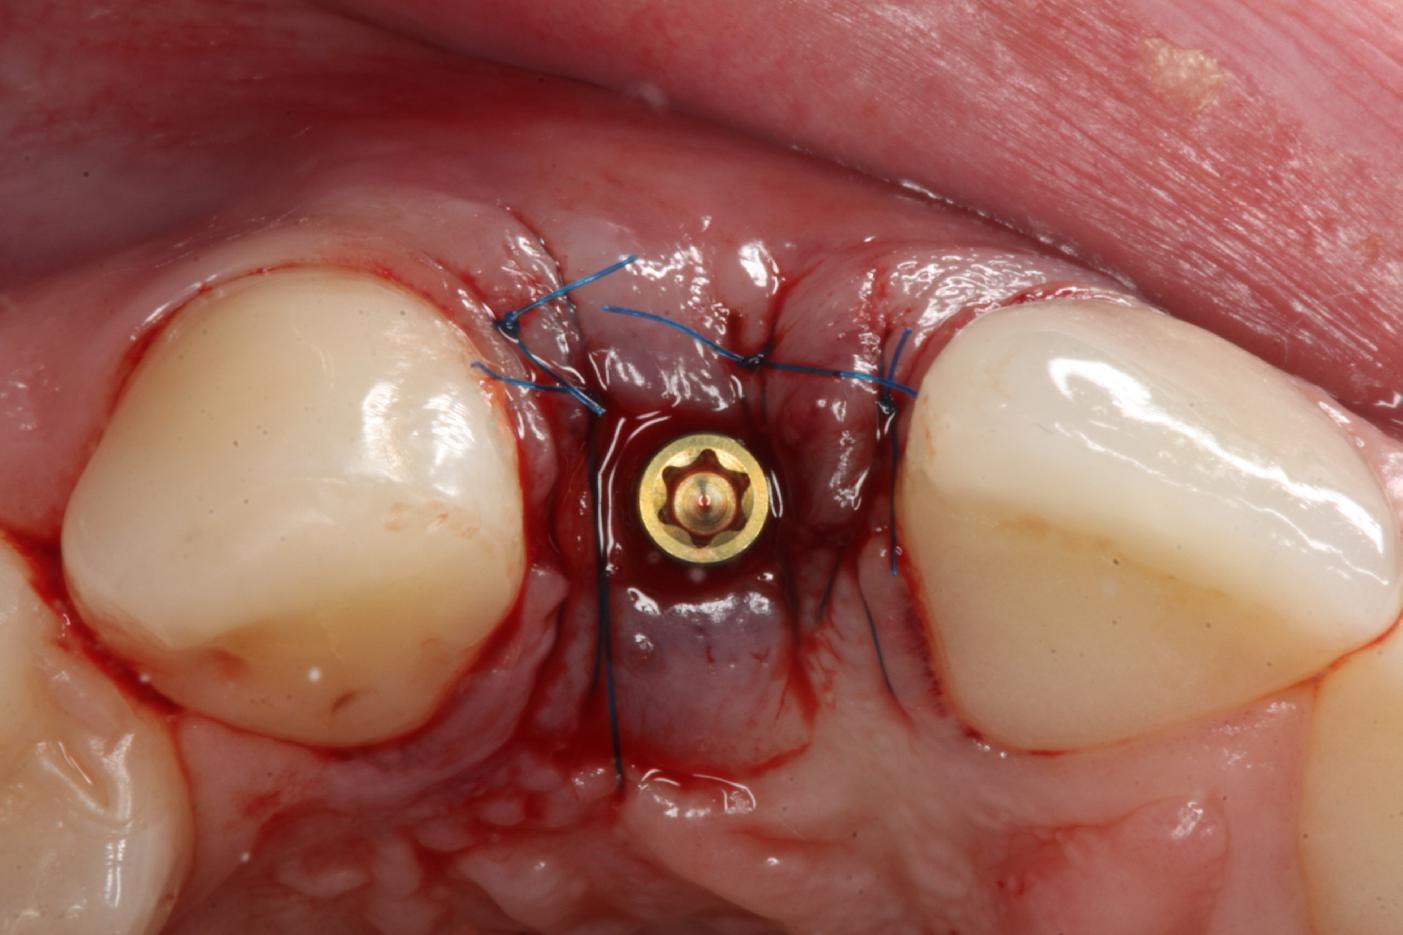

7/12 - Tension-free wound closure, occlusal viewSoft tissue thickening at immediate implant placement and GBR with mucoderm® and maxgraft® - Dr. A. Puisys